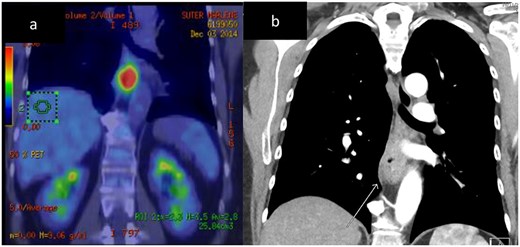

A 67-year-old (yo) woman was diagnosed with 1 month of dysphagia. She had no medical history. Endoscopic examination demonstrated a circumferential tumour in the mid to distal oesophagus with biopsies confirming a large cell neuroendocrine carcinoma (LCNEC) positive for CD56, Cga and cytokeratin (CK) 5 and 6. The Ki-67 index was 70%. Computed tomography (CT) demonstrated a thickened mid-oesophagus with lymphadenopathy of one para-tracheal node, measuring 1.9 cm (Fig. 2). Fluorodeoxyglucose (FDG) positron emission tomography (PET) scan indicated intense uptake of the mid-oesophageal mass without evidence of other metastases (Fig. 2). She underwent endoscopic ultrasound (EUS) and fine need aspirate (FNA) of the para-tracheal node which confirmed metastases. She was managed with neoadjuvant cisplatin, 5-fluourouracil (5-FU) and epirubicin. After 5 months following her diagnosis, she underwent a two-stage oesophagogastrectomy (Ivor–Lewis). Histopathology revealed a LC NEC with pathological stage of T3N1. One out of nine lymph nodes demonstrated metastases. No lymphovascular or perineural invasion was seen. The patient’s post-operative course was complicated by a pleural effusion, functional decline and swallowing difficulties; however, she improved and was discharged on day 18.

Case 1. CT and FDG-PET imaging of primary oesophageal tumour. Thickening of the oesophageal wall (a) and intense uptake on FDG-PET (b).